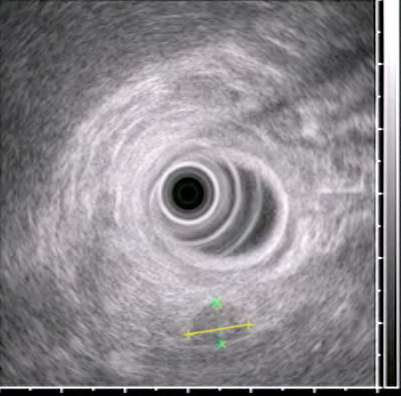

- Endoskopik USM kiçik törəmələrin və limfatik yayılmanın təyinində KT-dən daha həssasdır və mərhələnin təyini üçün istifadə edilə bilər.

- Endoskopik USM (ən həssas müayinədir)

İnsulinomaların yerini təyin etmək üçün ən həssas üsul hansıdır?

EndoUSM, PET-KT